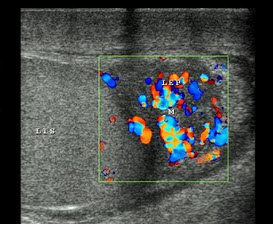

19、单项选择题

眶海绵窦瘘的超声表现()